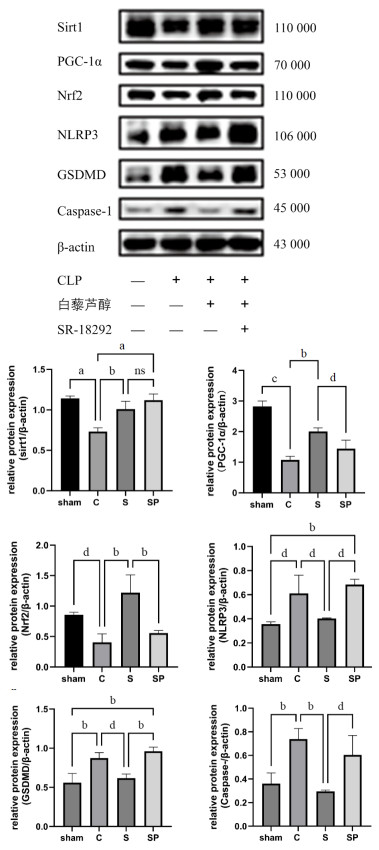

1.2.7 Western Blotting检测大鼠心肌Sirt1、PGC-1α、Nrf2、Caspase1、GSDMD、NLRP3蛋白表达水平称取适量心脏组织,BCA法测定心肌组织蛋白浓度,10%的SDS凝胶,上样,电泳结束后将蛋白凝胶转移到PVDF膜上,封闭洗膜,将膜与PGC-1α,Sirt1、Nrf2、Caspase1、GSDMD、NLRP3等蛋白一抗过夜孵育,Tris盐缓冲液(TBST)清洗,孵育生物素标记山羊抗兔的二抗1 h,TBST清洗后加超敏化学发光液(ECL),使用化学发光ECL显影系统成像。

C组大鼠心肌组织Sirt1、PGC-1α、Nrf2蛋白表达低于sham组(P < 0.05),而S组和SP组的Sirt1表达高于C组(P < 0.05),S组的PGC-1α和Nrf2蛋白表达高于C组(P < 0.05),SP组与S组的Sirt1表达差异无统计学意义(P > 0.05),SP组PGC-1α和NRF2低于S组(P < 0.05);而NLRP3、GSDMD以及Caspase1等焦亡相关蛋白在C组的表达高于Sham组(P < 0.05),S组的表达量较C组有所下降(P < 0.05),SP组较S组表达量升高(P < 0.05),差异均具有统计学意义。见图 3。

| 注:sham组为假手术组,C组为CLP模型组,S组为CLP+Sirt1激动剂组,SP组为CLP+Sirt1激动剂组+PGC-1α抑制剂组;a为P < 0.001,b为P < 0.01,c为P < 0.0001,d为P < 0.05,ns为差异无统计学意义 图 3 心脏组织中Sirt1、PGC-1α、Nrf2通路蛋白及GSDMD、NLRP3、NRF2蛋白表达水平 Fig 3 Expression levels of Sirt1, PGC-1 α, Nrf2 pathway proteins and GSDMD, NLRP3, Caspase 1 proteins in cardiac tissue |